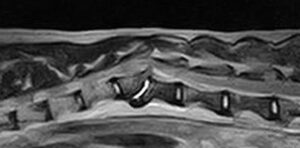

ワンちゃんが乳腺にできた複数のシコリを気にされて来院されました。bilateral mastectomyで対応しました。摘出後の病理組織検査の結果は、「R3-4間腫瘤:乳腺癌(複合型)」でそれ以外は「良性乳腺混合腫瘍」でした。無事元気に退院し、その後再発もなく経過は良好です。よかったね。